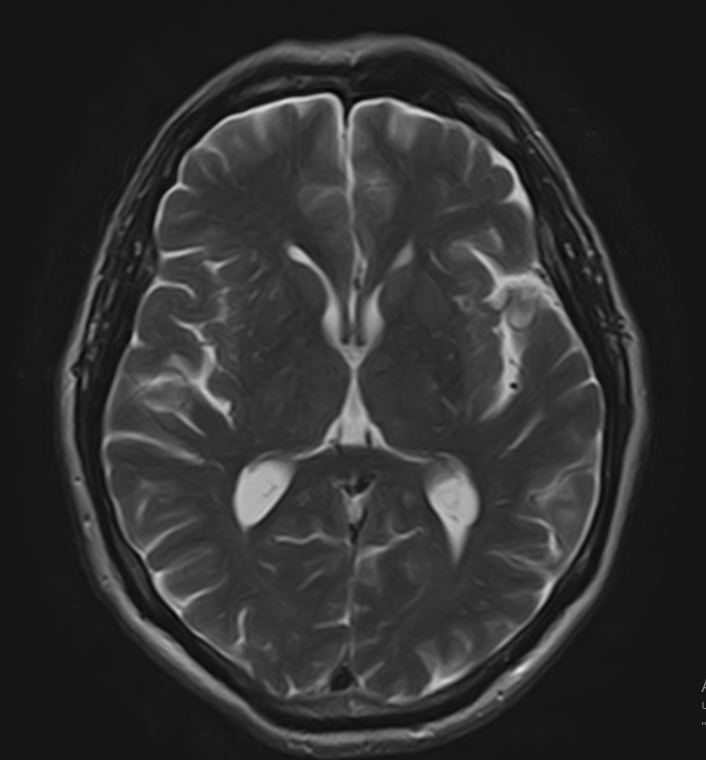

МРТ головного мозга является высокоинформативным методом исследования центральной нервной системы, который дает возможность оценить состояние всех структур головного мозга и поставить правильный диагноз. Стандартную МРТ головного мозга дополняет МР-венография, которая позволяет получить детальную картину строения и функционального состояния венозной системы мозга.

В клинике «Доступная медицина» проводится МРТ головного мозга и МР-венография головного мозга на современном аппарате TOSHIBA VANTAGE TITAN 1,5 Тесла, который обладает высокой чувствительностью и соответствует всем мировым стандартам качества диагностики. Напряженность магнитного поля 1,5 Тесла обеспечивает высокую четкость изображения и позволяет выявлять заболевания на ранних стадиях развития. Процедура МРТ безопасна, так как томограф не испускает рентгеновского излучения, полностью безболезненна и имеет доступную стоимость.

• очаги ишемического и геморрагического инсульта, область поражения, признаки отека головного мозга, стадию развития заболевания;

• доброкачественные и злокачественные новообразования, их точную локализацию, стадию развития процесса, проводить динамическое наблюдение за опухолевым процессом на фоне лечения;

• признаки демиелинизирующих заболеваний (рассеянный склероз), выявить очаги поражения миелиновой оболочки нервных волокон, определить стадию заболевания;

• характерные признаки дегенеративных заболеваний головного мозга (болезнь Альцгеймера, старческая деменция, болезнь Паркинсона), определить изменения коры головного мозга и подкорковых структур;

• поражение структур головного мозга на фоне травм, гематомы головного мозга;

• изменения, характерные для психических расстройств различного генеза (эндогенных и экзогенных), после вирусных инфекций, черепно-мозговых травм, отравлений токсическими веществами, на фоне наследственных заболеваний;